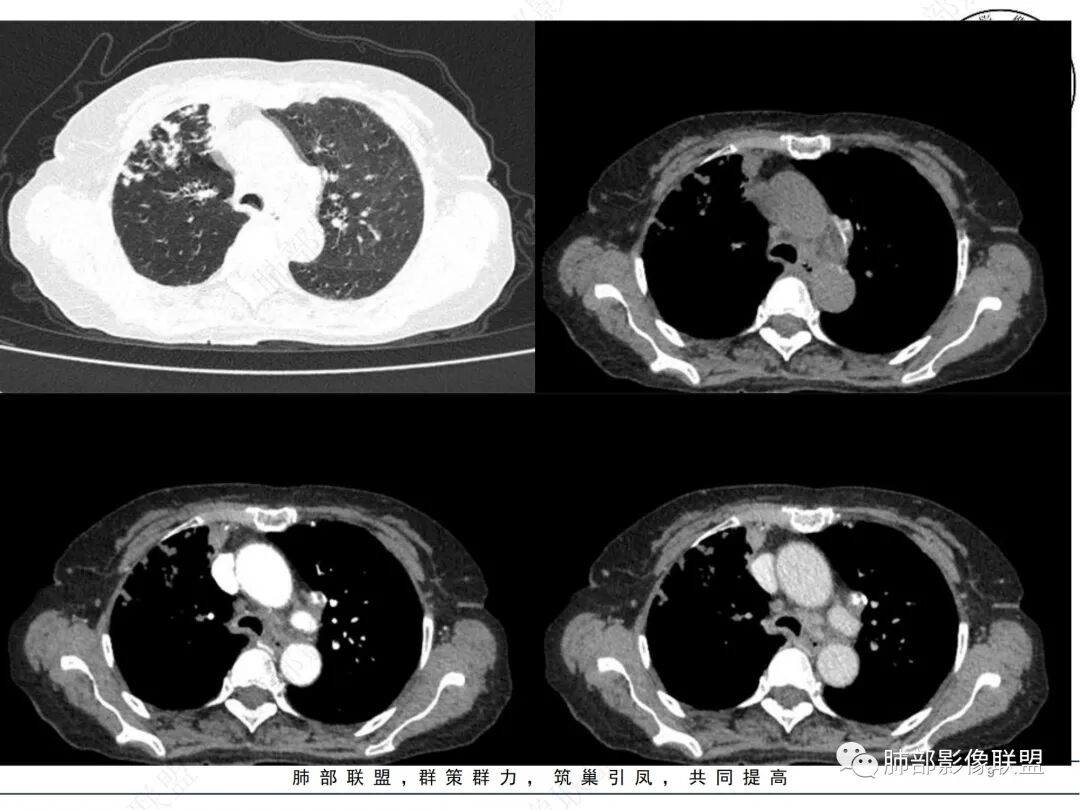

2. CT示右肺上叶多发斑片状实变影,结节影,集群散落,夹杂条索影,边界可分辨,有沿支气管血管束分布趋势,可见树芽征。病灶新旧不等、密度不均。右上叶支气管壁不均匀节段性增厚狹窄,斑点状钙化。纵隔旁部分肺组织含气不良,并显示轻度扩张支气管。病灶邻近胸膜增厚,轻度强化。

3.余双肺显示马赛克灌注、轻度气肿。双肺散在微小实行密度结节影,边界清楚。

4.纵隔多发增大淋巴结,部分融合、钙化。

成簇分布斑片影、结节影、树芽征,边界较清楚,新旧不等,节段性支气管壁增厚伴钙化,管腔狭窄,纵隔及肺门淋巴结增大钙化等都较符合“继发性肺结核、支气管内膜结核”诊断。